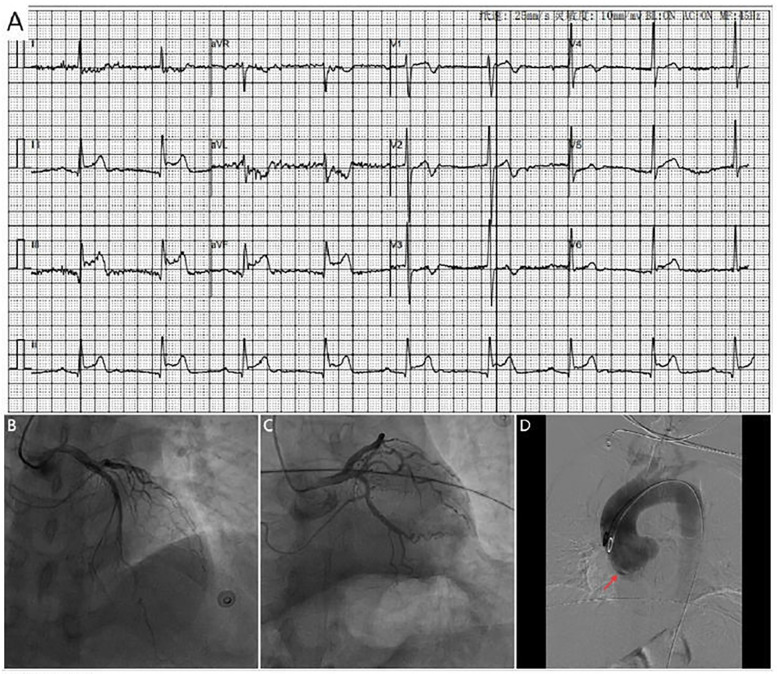

定位性瓦尔萨尔瓦窦(SOV)夹层是一种罕见但危险的情况,表现为下st段抬高型心肌梗死(STEMI)。我们提出了两个病例,其中计算机断层血管造影(CTA)是必不可少的,以确定SOV夹层。在第一个病例中,CTA证实右侧SOV局部夹层。由于最初的诊断困难和家庭的犹豫,手术血运重建被推迟,最终导致了致命的结果。二是血管内超声(IVUS)证实右冠状动脉(RCA)外源性压迫,急诊支架植入术后冠脉血流恢复,保守治疗取得了良好的临床效果。这些病例强调了当血管造影结果与临床表现不一致时,早期CTA的关键作用,IVUS在确定冠状动脉闭塞病因方面的应用,以及及时血运重建的重要性。

Located sinus of Valsalva (SOV) dissection is a rare but critical condition that presents as inferior ST-segment elevation myocardial infarction (STEMI). We present two cases in which computed tomography angiography (CTA) was essential in identifying SOV dissection. In the first case, CTA confirmed a localized dissection of the right SOV. Surgical revascularization was delayed owing to initial diagnostic challenges and the family's hesitation, which ultimately led to a fatal outcome. In the second, intravascular ultrasound (IVUS) confirmed extrinsic compression of the right coronary artery (RCA), and following emergency stent implantation, coronary blood flow was restored, conservative treatment achieved a favorable clinical outcome. These cases highlight the pivotal role of early CTA when angiographic findings are incongruent with the clinical presentation, the utility of IVUS in determining the etiology of coronary artery occlusion, and the critical importance of timely revascularization.